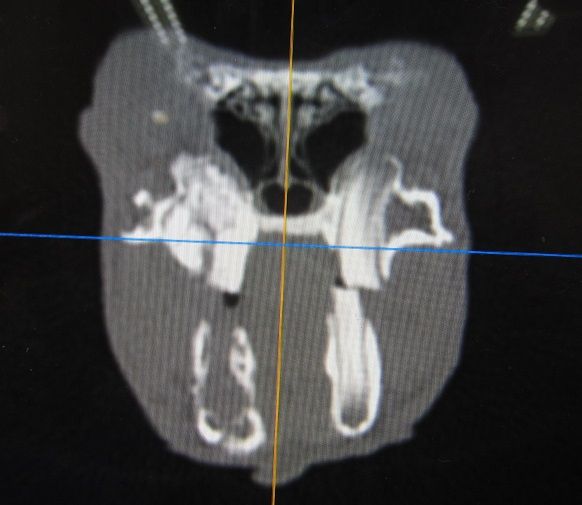

特殊な機具を使って骨に穴をあけてます。

ピンセットで一つずつ取り出してる様子、当初、左だけの予定でしたが右もけっこうあったので、

両方穴をあけました、とな💦

取り出せたもの、かなりたくさんです。